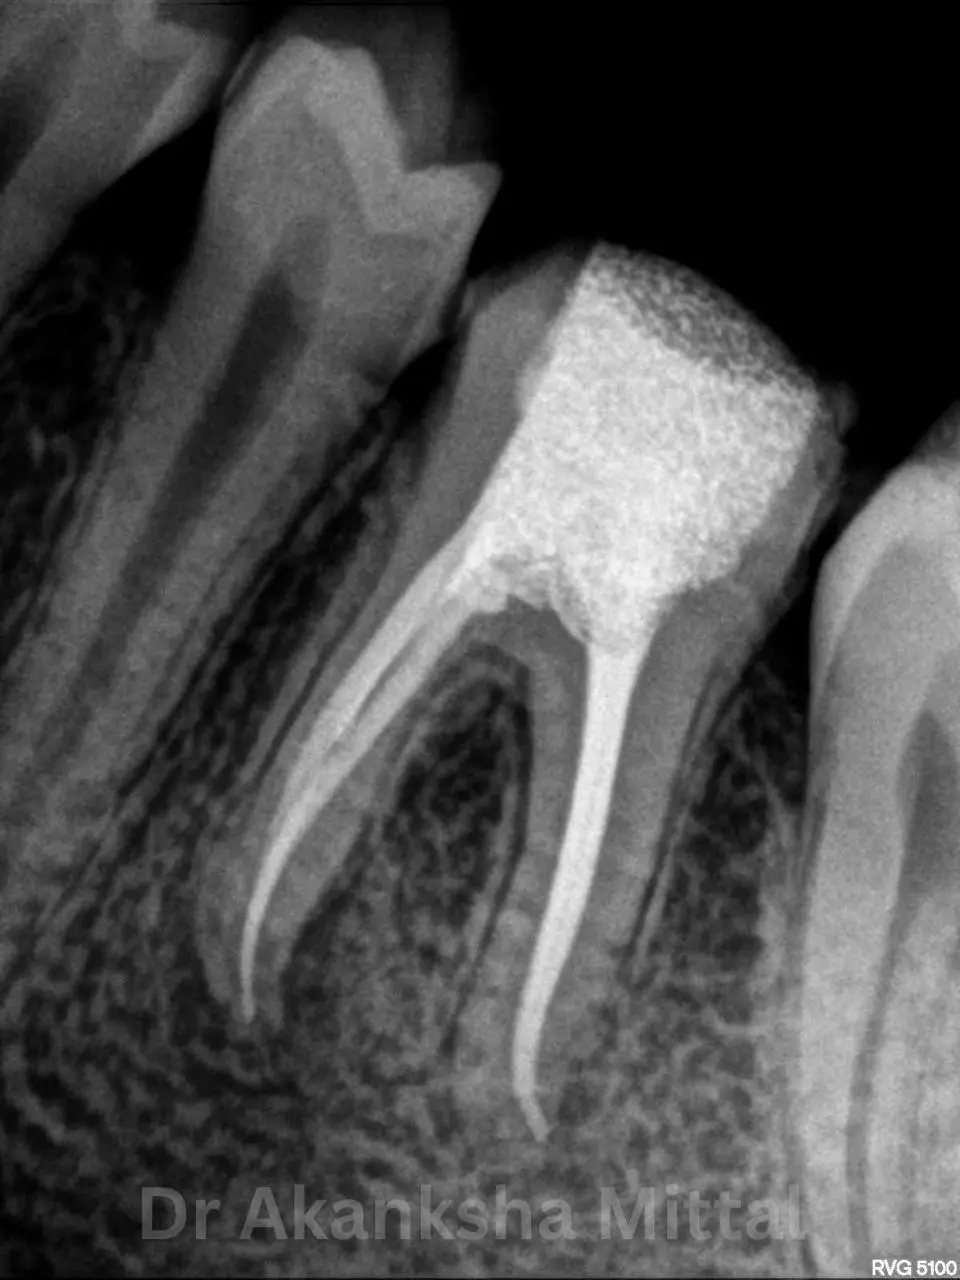

At Teethtime, we specialise in modern root canal treatment designed to eliminate tooth pain and preserve your natural tooth. Under the expert care of Dr Akanksha Mittal (MDS), our clinic uses advanced rotary technology to make your experience gentle and effective.

A root canal is recommended when the inner pulp of the tooth becomes infected due to deep decay, cracks, or injury. If left untreated, the infection can cause severe pain and may lead to tooth loss.

Our goal at Teethtime is to remove the infection and restore your tooth’s strength and function using the most advanced dental technology available in Chandigarh.

Precision Matters

Every procedure at Teethtime is supervised by MDS Specialist Dr. Akanksha Mittal, ensuring the highest standards of clinical excellence.